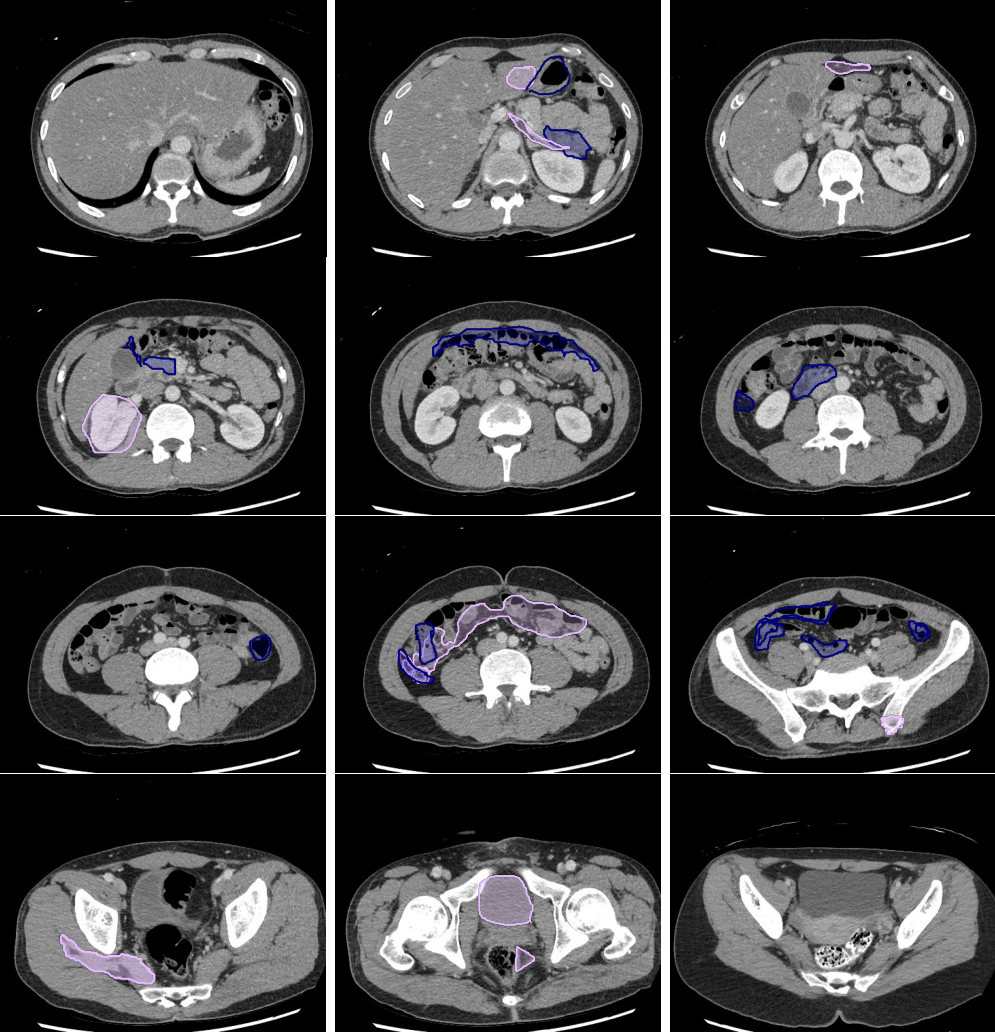

Legend

Slice 1

Slice 2

Slice 3

Slice 4

Slice 5

Slice 6

Slice 7

Slice 8

Slice 9

Slice 10

Slice 11

Slice 12